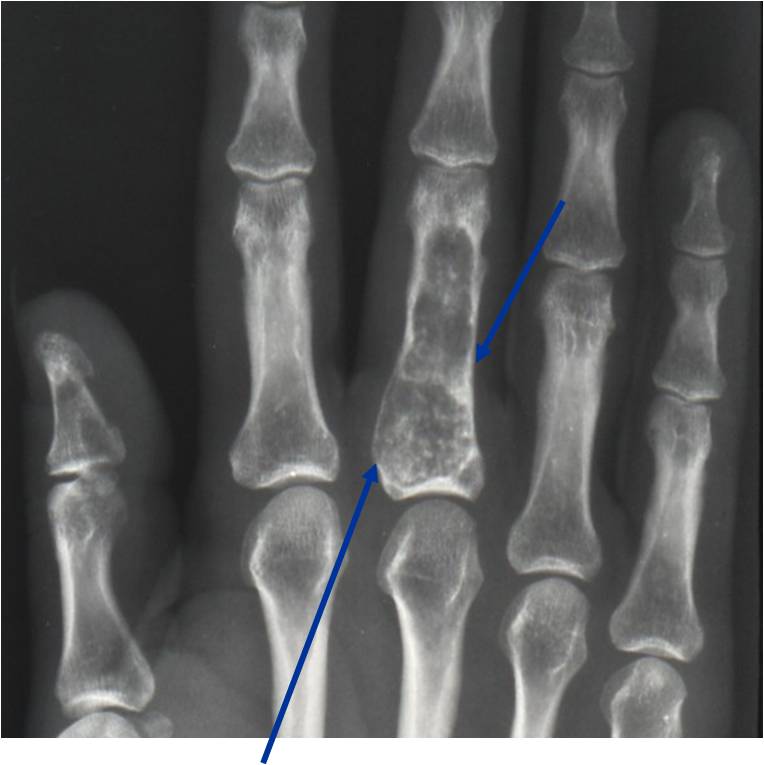

Radiographic Presentation

- Localized, radiolucent defect usually with punctate calcifications

- Calcifications are typical but not always present

- Matrix may demonstrate various degrees of calcification

- Calcifications are stippled, punctate, popcorn like calcifications and “Ring and Arc” calcifications

- Cartilage tumors grow in a lobular manner. The perimeters of the lobules undergo

- enchondral ossification that may calcify. If the entire perimeter of the lobule calcifies it appears

- radiographically as a “Ring”. If a portion of the perimeter of a lobule calcifies it forms an “Arc” on

- an X-ray.

- May be located centrally or eccentrically

- Grows eccentrically or concentrically (phalanges)

- Cortex may be scalloped and thinned in the phalanges

Plain X-Ray:

- Geographic lytic lesion

- Central often metaphyseal in long bones

- Can be eccentric also

- Expansile remodeling with thinned cortex

- Chondroid matrix with calcifications in majority of tumors

- Approximately 20% have limited or no calcifications

Imaging characteristics:

- Lesions seen in infancy

- Typical enchondromas

- Geographic IA-IIB with expansion

- Lytic columns from epiphyseal plate

- Chondroid matrix calcification

- Growth disturbance and bowing